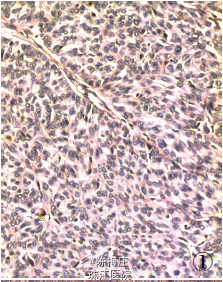

最后诊断:右乳神经内分泌癌;结肠腺癌;左侧卵巢Brenner 瘤。

遂行右乳肿物切除术+ 乙状结肠癌切除术及左侧附件切除术。术中所见:右乳肿物分叶状,与周围界清;乙状结肠肿物与周围无粘连;左侧卵巢肿物包膜完整,未见腹水。术后病理显示右乳腺内分泌癌,乙状结肠腺癌,左侧卵巢Brenner 瘤。